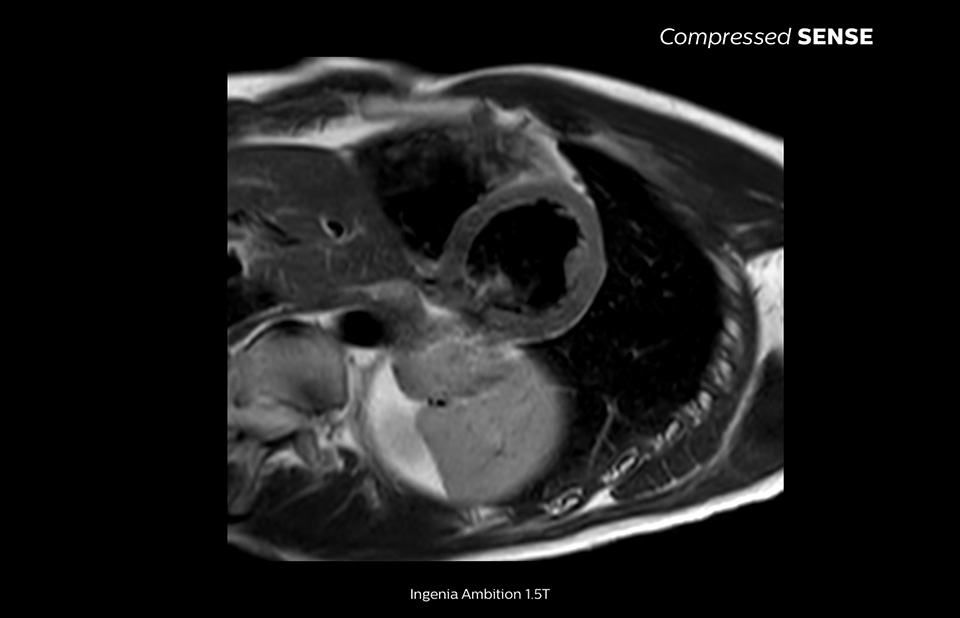

4.8 sec breath hold time

Since short breath hold times make it easier for our patients to comply, the failure of breath holding largely disappeared.

At our facility, we found in Cardiac MR fewer breath holds are now needed, or breath hold times are shortened."

Dr. Takashi Koyama, MD, PhD, Diagnostic Radiologist and Director of the Department of Radiology Center and Diagnostic Radiology, Kurashiki Central Hospital, Japan

A 15- or 16-second breath-hold is tough for many cardiac patients. With Compressed SENSE we actually have protocols now that can get that below 10 seconds. It’s a lot easier to get through for a patient, and patients are a lot more satisfied with the experience.”

Trevor Andrews, Ph.D., MR Physicist, University of Vermont Medical Center, USA

The MRI staff at Kurashiki Central Hospital incorporated Compressed SENSE into most of the brain, spine, abdominal, and cardiac examination protocols on their Ingenia 1.5T, resulting in fast and high-quality MRI scans, which is welcomed by patients and staff.